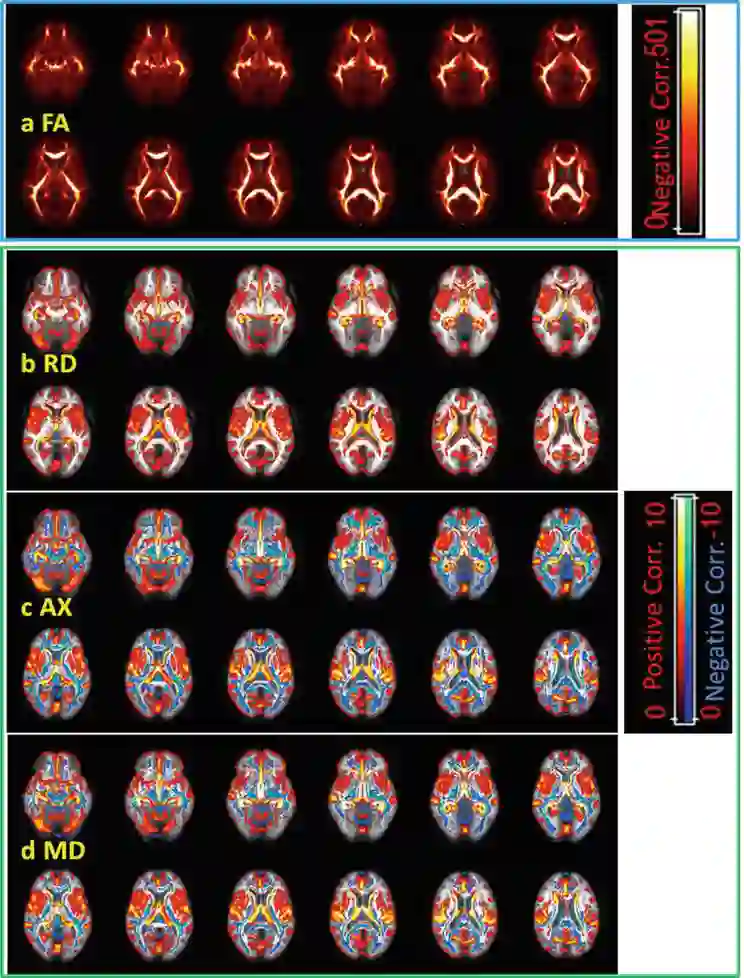

考虑到许多与年龄相关的风险,包括血管和神经炎症的增加,以及可能混淆基准功能磁共振参数图像,在相对较短的时间内揭示个体水平上的脑功能和微观结构变化尤其重要。细胞水平的轴索损伤和/或脱髓鞘以及弥散的中观水平物质异常聚集和结构/功能异常可在短的亚急性/急性期发生,而与年龄纵向变化相关的文献仅局限于我们以前的fMRI发现。纵向数据用来描述这些多参数,包括随机截距和个体间隔。性别交互作用对DTI分数各向异性(FA)和扩散系数均无显著影响。区间有效区域表现出FA的纵向变化,径向扩散系数(RD)/轴向扩散系数(AX)值与截面数据的老化结果相似。在DTI和fMRI指标之间,以及成像和神经认知数据(包括速度和记忆力)之间,发现了显著的相关性。我们的结果表明,年龄、性别和载脂蛋白E (APOE)基因型对结构和功能连接在短间隔和横断面范围内的显著和一致的影响,以及相关的神经认知功能。